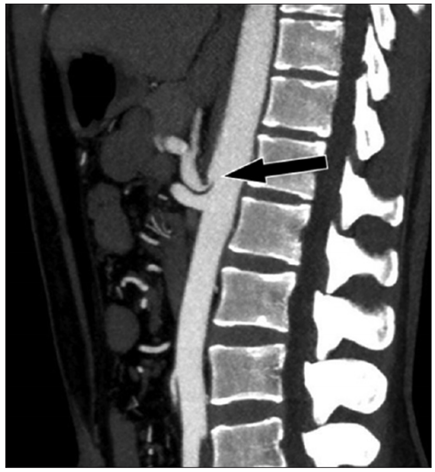

Vasos abdominais e pélvicos podem ser comprimidos por estruturas anatômicas que estejam próximas ou podem comprimir vísceras ocas adjacentes, por vezes caracterizando algumas síndromes de compressão vascular. O corte sagital de tomografia computadorizada (com contraste venoso) abaixo é de uma paciente de 25 anos, com queixas de dor epigástrica pós-prandial e perda de 8 kg nos últimos 2 anos.

Assinale a alternativa que contém o correto diagnóstico deste paciente.